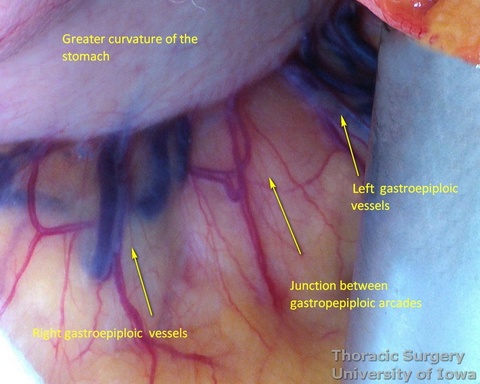

- The gastrocolic ligament is incised in its avascular portion between the terminal branches of the right and left gastroepiploic vessels, and the lesser sac is entered.

- The gastrosplenic ligament is divided towards the hiatus, taking care to stay away from the gastroepiploic arcade.

- The greater curvature of the stomach is then mobilized towards the pylorus, dividing the gastrocolic ligament no closer to than 1.5–2 cm to the right gastroepiploic vessels, while protecting the vessels with the fingers of the retracting hand. In morbidly obese patients the right gastroepiploic artery may not be visible or palpable. A Doppler probe is used then to identify its course and origin from the gastroduodenal artery.